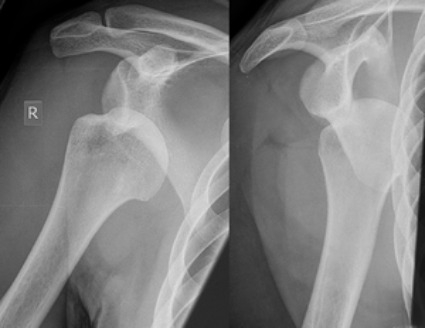

"ลูก้า ซีดาน ต้องเข้ากระบวนการผ่าตัดบริเวณข้อไหล่ขวาที่ร้าว โดยกระบวนการจะมีขึ้นที่โรงพยาบาล ฌอง แมร์กโมซ์ ที่เมืองลียง ประเทศฝรั่งเศส โดยนายแพทย์ ชิลล์ส วอลค์"

"ภายใต้คำปรึกษาของผู้เชี่ยวชาญจากศูนย์การแพทย์ เรอัล มาดริด ซานีตาส เป็นผู้ควบคุม"

ฟิล์มเอ็กซ์-เรย์ บริเวณข้อไหล่ขวาที่ร้าว